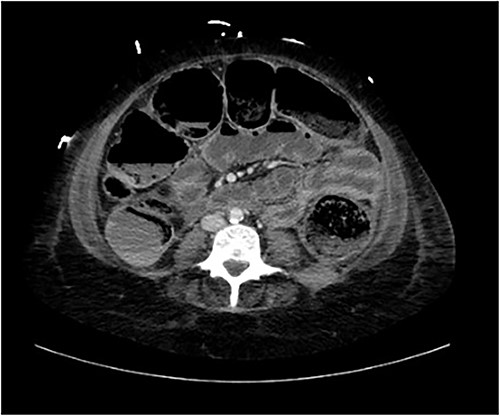

A provisional diagnosis of a ‘bowel obstruction’ was made and she was admitted to hospital for conservative management with nasogastric drainage, intravenous hydration, and aperients. Over the following 24 h, her abdominal pain remained severe and further surgical review was sought. At this stage she exhibited a distended, firm, exquisitely tender abdomen. A repeat CT at this time once again demonstrated faecal loading, normal bowel wall enhancement, and no perforation (Figs 1 and 2). At this stage she was fasted and consented for an exploratory laparotomy under general anaesthesia. She proceeded to theatre after reversal of her INR with prothrombinex and vitamin K.

Axial view of CT abdomen demonstrating normal large bowel wall enhancement with faecal loading.